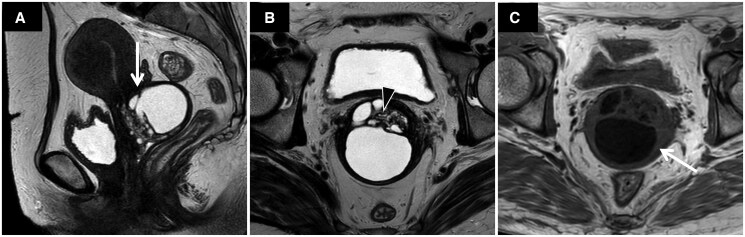

Methods: We retrospectively reviewed T1-weighted (T1WI) and T2-weighted images (T2WI) and measured the lesion volume, the ratio of cervical canal position at the maximum cross-section (deviation ratio), the ratio of the lesion's centre within the craniocaudal length (longitudinal location ratio), distance from the internal and external os, maximum cyst diameter, and signal intensities of the cyst content on T1WI and T2WI (T1 and T2 ratios). These parameters were compared between GAS or LEGH and OBC, where OBC was clinically suspected of LEGH.

Results: Seventeen patients with GAS, 18 with LEGH (52 ± 11 years), and 42 with OBC (45 ± 10 years) were included. GAS/LEGH were larger in volume (29.25/15.24 cm3, P < .001), and had a greater deviation ratio (0.82/0.84, P < .001), shorter distance to the internal and external os (3.4/3.6 mm, P = .040, and 3.3/3.3 mm, P = .003, respectively), and a lower T1 ratio (1.08/0.91, P < .001). The area under the curve (AUC) of these parameters using their respective optimal cut-off values was 0.818, 0.756, 0.629, 0.711, and 0.731, respectively. When 3 or more positive criteria were considered, the AUC increased to 0.896.

Conclusions: Compared with OBC, GAS/LEGH displayed a larger volume, cervical canal deviation, proximity to the internal and external os, and a lower T1 ratio of cyst content.

Advances in knowledge: Considering both the lesion and its relationship to the cervical canal is imperative for differentiating between the conditions.